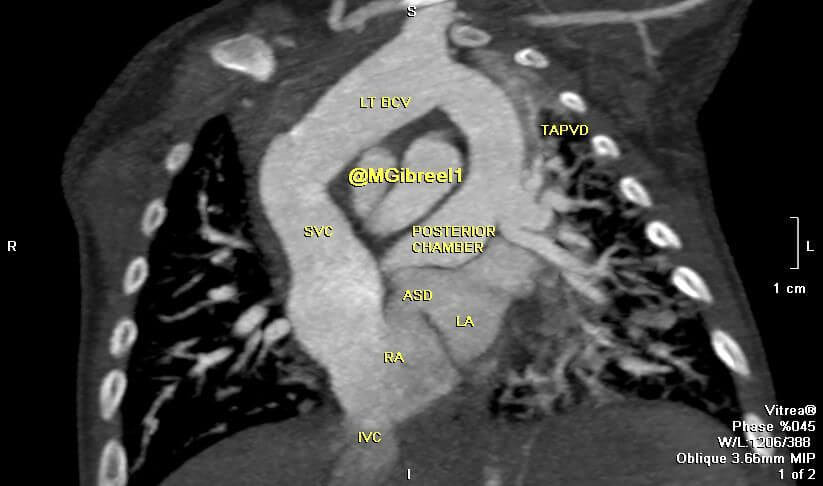

Unobstructed TAPVR supracardiac type